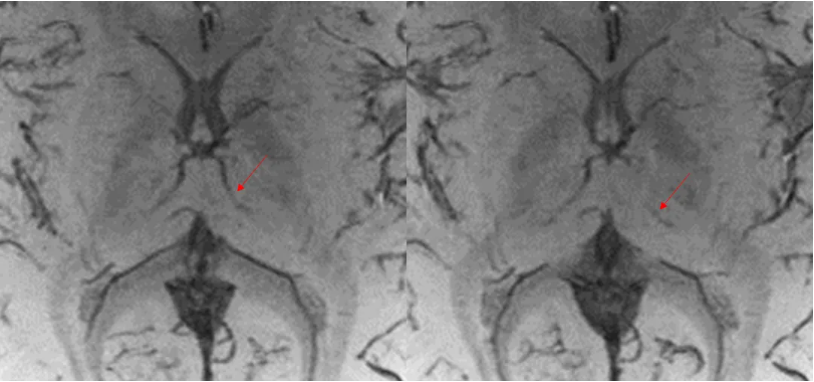

是不是静脉畸形, 整一个磁敏感成像SWAN:2/-1mm

SWAN进行厚层(6mm)最小信号强度投影重建(MinP)效果, 一根正常的小静脉在此区域走行,其余未见显著异常。

要么再试试薄层DWI: MUSE DWI b1000:FOV = 20 , 160(freq)× 512(phase),2 /0mm。 这根狡猾的小静脉终于露出庐山真面目。

常规DWI层厚5 / 1 mm,160 × 192;分辨率已经挺高的了。但是仍旧会存在严重的容积效应。

这个患儿扫描到MP- RAGE的时候,已经陷入深度睡眠(虽然没有吃药)。所以,我们加扫了SWAN和高清MUSE,2mm,矩阵512。为了降低容积效应,我们已经使出了洪荒之力。